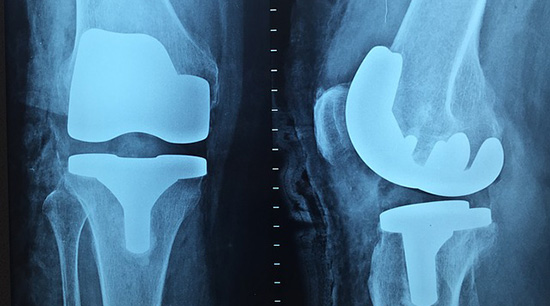

如果真的是關節損傷、老化,出現韌帶損傷或者關節炎等等問題的話,在關節咔咔響的同時,還會出現關節疼痛、關節腫大的問題,而且這種疼痛、腫大並不會輕易消失。

不管是多保護關節,隨著年齡增大,關節的使用年限一長,關節都會出現被磨損的問題。處於關節腔內的兩端骨頭上面覆蓋著軟骨,我們運動的時候軟骨會被逐漸磨損,所以為了保護軟骨、關節,每周至少鍛鍊兩次,而且運動之前要做熱身,促進滑液的分泌。減輕體重,能減少我們對於關節的壓迫,為關節減負,同時要記得減肥的時候別用爬樓的方式運動,防止磨損膝蓋。